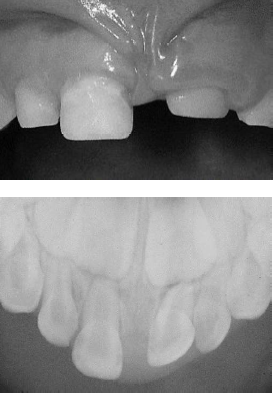

Acervo pessoal.

Com base nas imagens apresentadas e considerando os aspectos clínico e radiográfico de uma criança de 4 anos de idade, 20 dias após luxação intrusiva completa, julgue os itens a seguir.

A imagem radiográfica é altamente sugestiva de deslocamento palatino da raiz do dente 61, o que indica aproximação com o germe do dente 21.